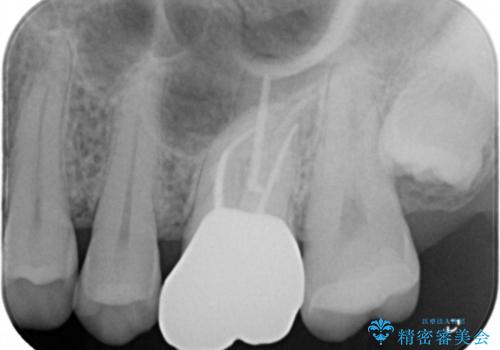

- 左上7番の銀歯をセラミックにやり変え希望の患者様です。

切削量・形態からセラミックインレーでの治療を計画しました。

銀歯とその直下のう蝕を除去した後、CRにて裏層しています。

インレー装着の際はラバーダムを使用しています。